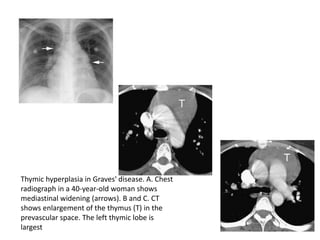

Thymic hyperplasia in Graves' disease. A. Chest

radiograph in a 40-year-old woman shows

mediastinal widening (arrows). B and C. CT

shows enlargement of the thymus (T) in the

prevascular space. The left thymic lobe is

largest